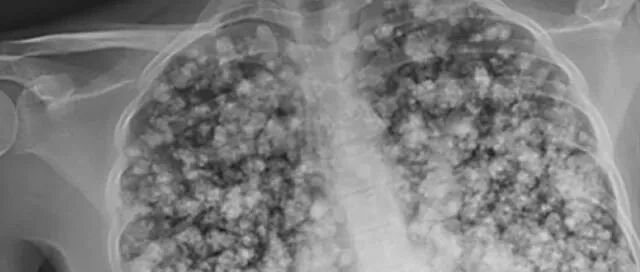

在医院为他进行了仔细检查后,

惊人的发现,

他的双肺已经彻底沦为:

爆米花肺(Popcorn Lung)!

他的肺部几乎所有的小气道以及全部发炎并被阻塞,

唯一的治疗方法就是,